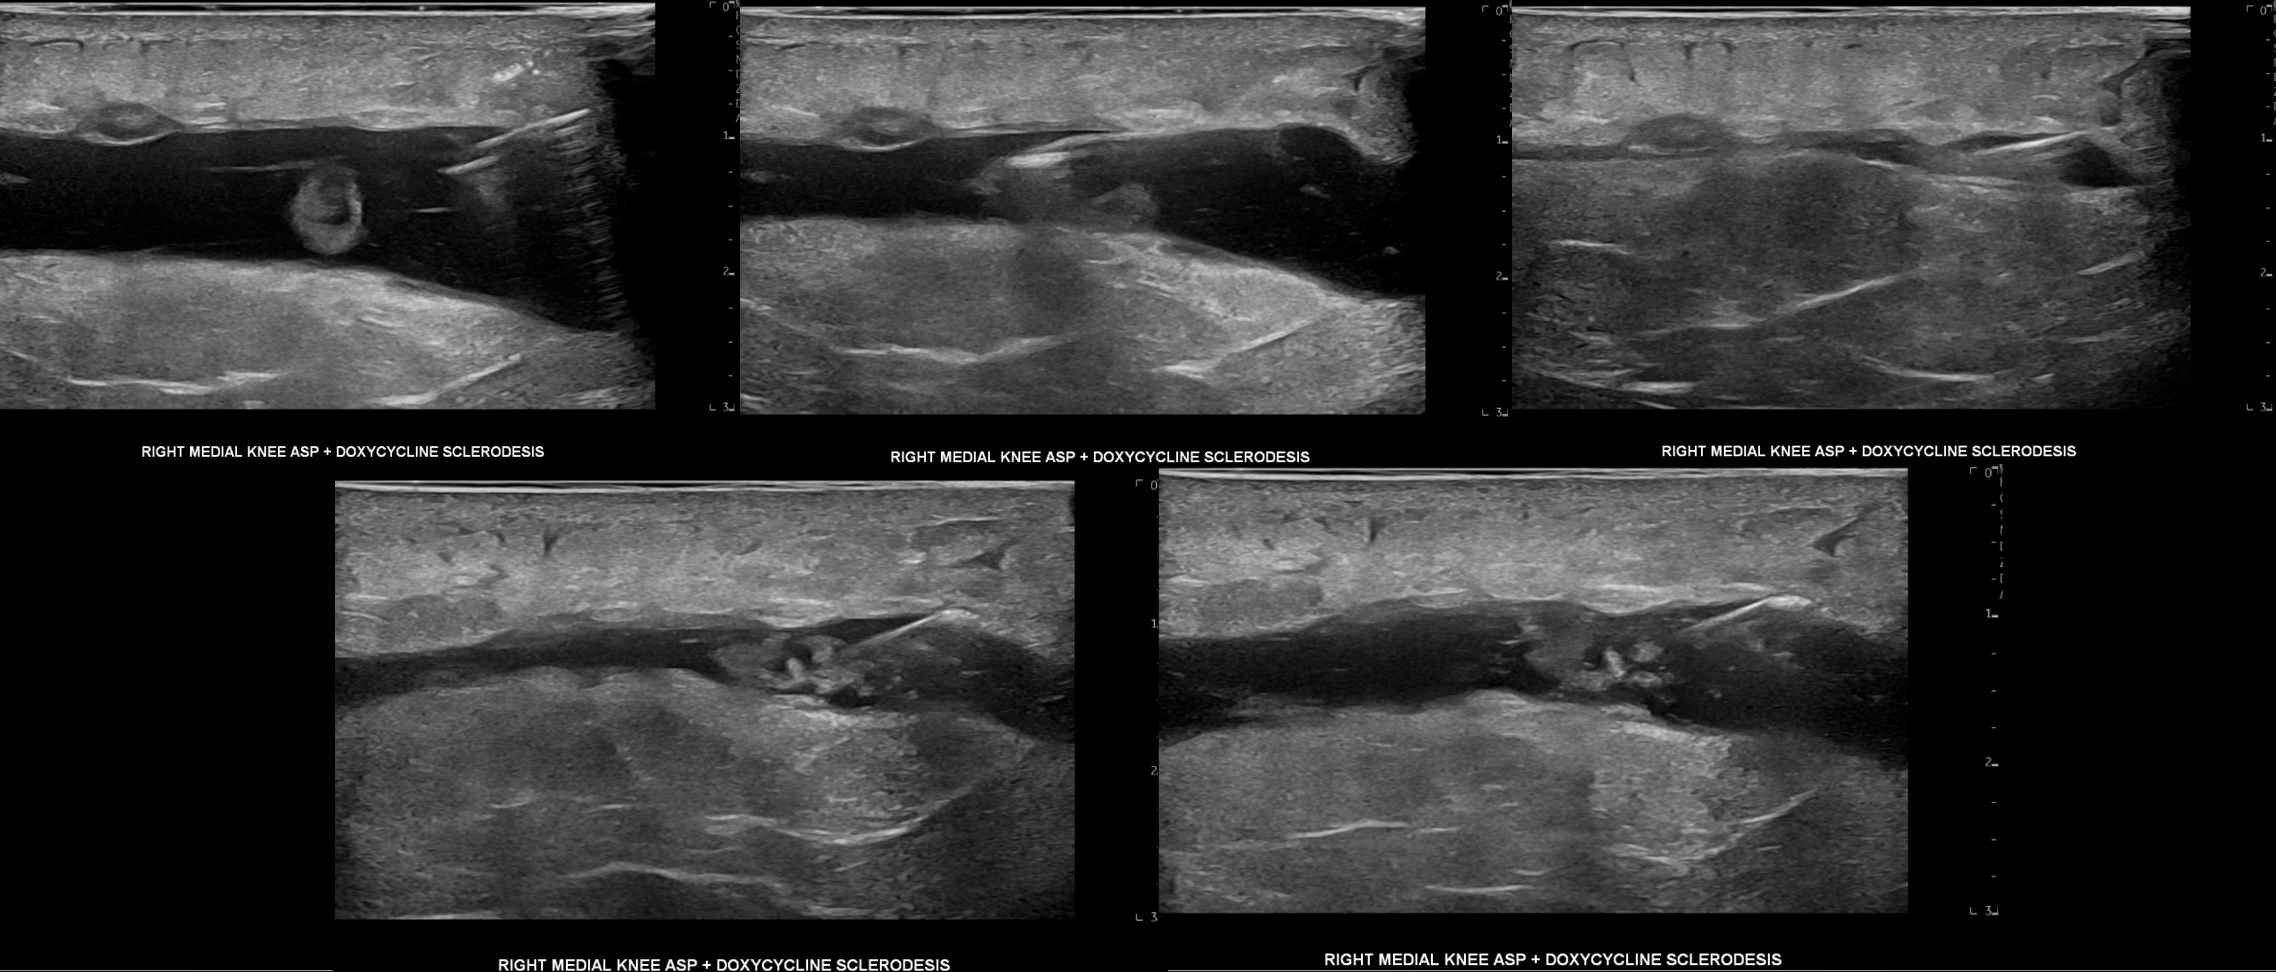

Unlabeled short axis progression of Morel-Lavallee lesion aspiration of 37 mL of serous fluid followed by doxycycline sclerodesis at eight months post-injury.